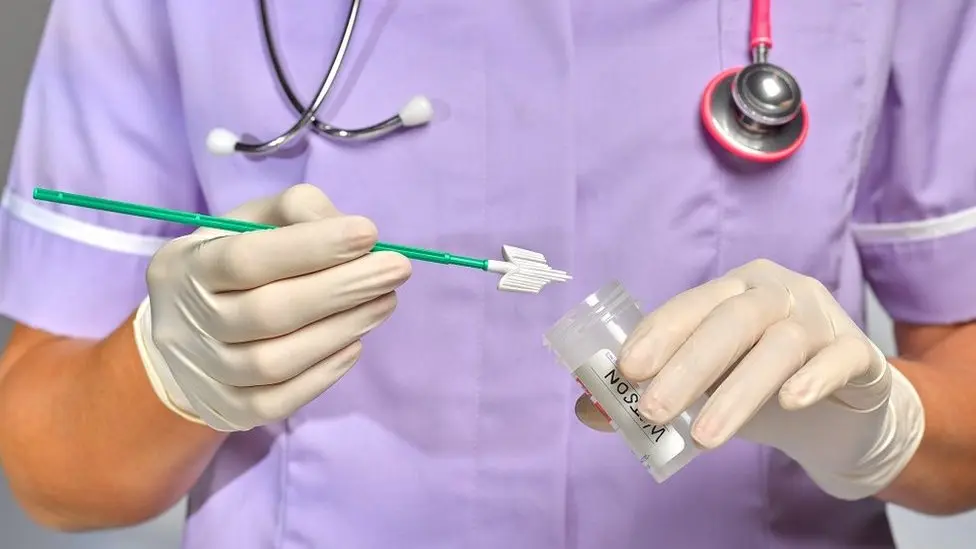

Cervical Health: Why Regular Screening Matters for Women

Cervical Health: Why Regular Screening Matters for Women Home / Women’s reproductive health involves many important preventive practices, and one of the most essential among them is cervical screening. This medical test plays a critical role in identifying early changes in cervical cells before they develop into serious health conditions. The cervix, located at the […]